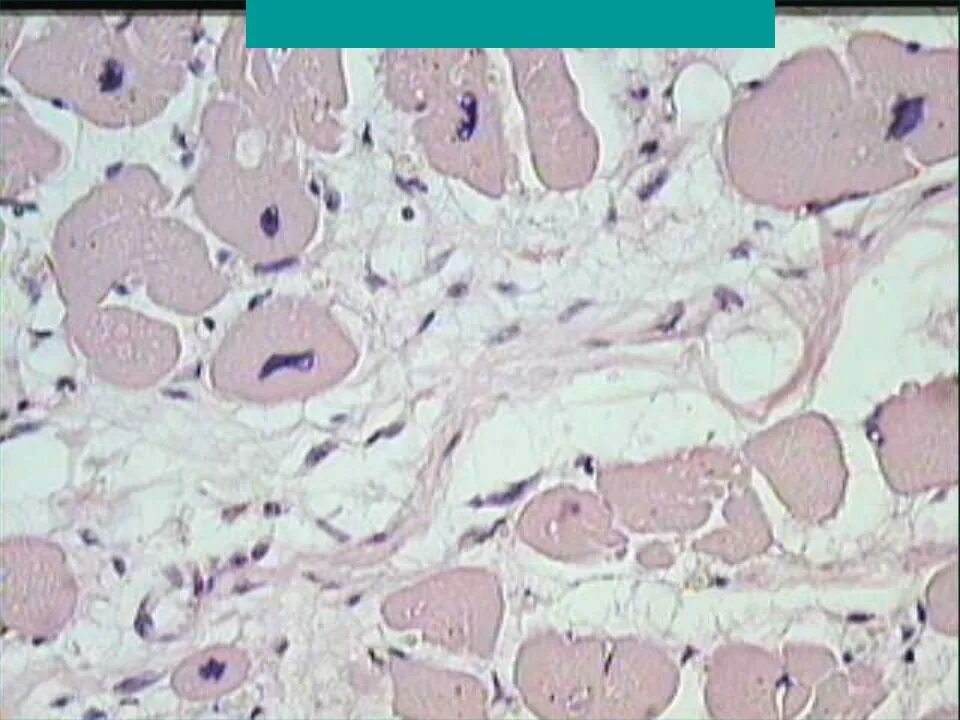

Миокардический кардиосклероз